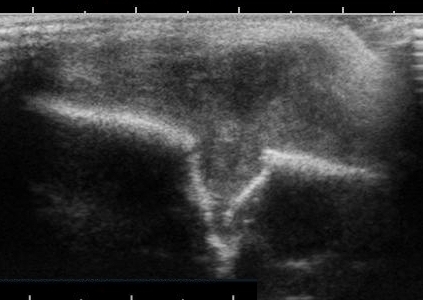

Ultraschallschnitt eines eosinophilen Granulomes am Schädel bei einem 1 jährigen Kind mit großem Weichteiltumor und deutlich kleinerer, unterminierender Destruktion der äußeren Teile der Schädelkalotte

Foto: Kinderradiologie Olgahospital Klinikum Stuttgart